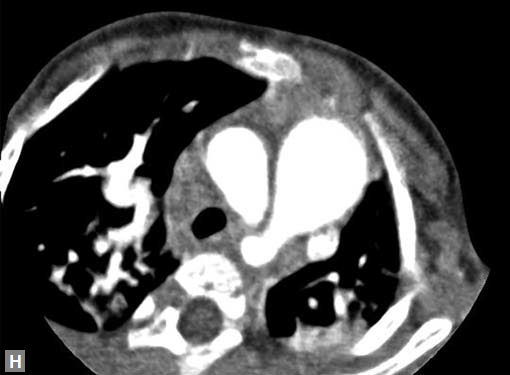

Pericardial effusion may accompany type A dissection.

Hemopericardium is the dreaded complication of leaking

type A dissection (Figs 19S to V). The type B dissection can

cause small foci of atelectasis in adjacent lungs and should

not be mistaken for leak. Type B dissection can leak and cause

left hemothorax.

Any part of aorta can get affected by aneurysms. Focal

dilations can be saccular or fusiform. Atherosclerosis is

the most common cause. Tubercular and other infective

aneurysms, traumatic ones are also uncommonly seen. Size

of the aneurysm, proximity to origin of main vessels, relation

with branching and bifurcation, presence of mural thrombus

are the critical information sought on CT.

Contained leak, rupture are the feared complications.

Aortoenteric fistula is a rare but potentially catastrophic

complication. Aneurysmal dilation is common in ascending

aorta (Figs 19W to Y).

Figs 19A to Y (A to C) Scannogram (A), plain (B) and contrast study (C) show partial anomalous pulmonary venous connection; (D to F) Heterotaxy; (G) Aortic occlusion; (H and I) Aortic stents; (J) Aortic dissection with ‘Benz’ sign due to second dissection within the true lumen; (K, L and M) Aortic dissection with thrombus in pseudolumen following catheter angiogram; (N) Aortic dissection involving common carotid arteries and subclavian artery; (O, P, Q and R) Aortic dissection with right renal artery arising from true lumen and left renal artery from false lumen; (S, T, U and V) Stanford B dissection with extension Y to iliac vessels; (W to Y) Aneurysmal dilation of ascending aorta